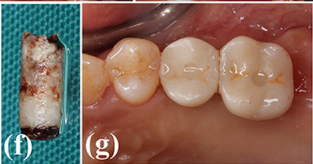

Case photos provided by: Customized three-dimensional printed ceramic bone grafts for osseous defects: a prospective randomized study.

Serial clinical and radiographic images of the experimental group receiving customized 3D-printed ceramic bone grafts. (a ) preoperative panoramic radiograph of tooth #37; (b ) postoperative panoramic radiograph after surgical extraction of tooth #37 with GBR using OSTEON 3D and Collagen Membrane; white asterisk indicates grafted bone material; (c ) CBCT image before the implant placement at visit 5; (d ) panoramic radiograph after implant fixture installation; (e ) panoramic radiograph after final implant final prosthesis; (f ) clinical photo of bone grafting; (g ) 3D digital image of design for fabrication of customized 3D printed ceramic bone grafts (OSTEON 3D).